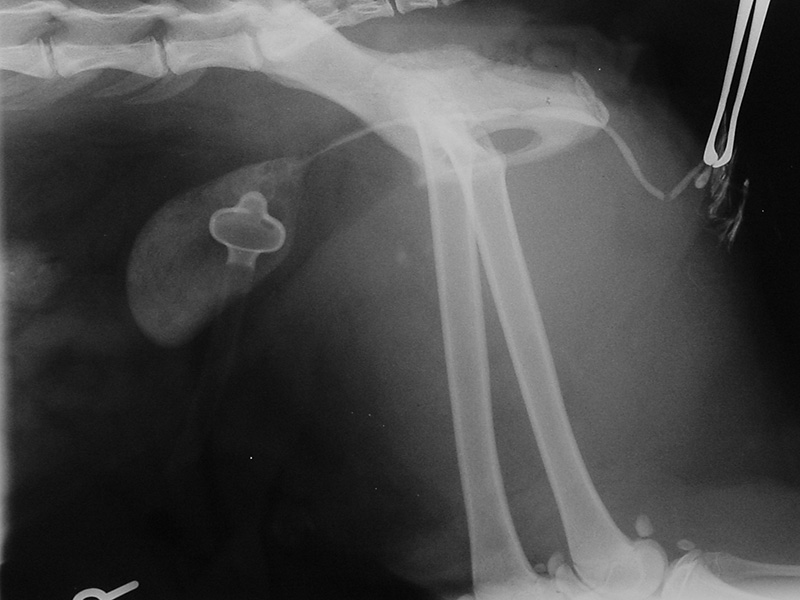

- Imaging the urinary tract: X-rays, retrograde studies or ultrasound? (César Sánchez Jiménez)